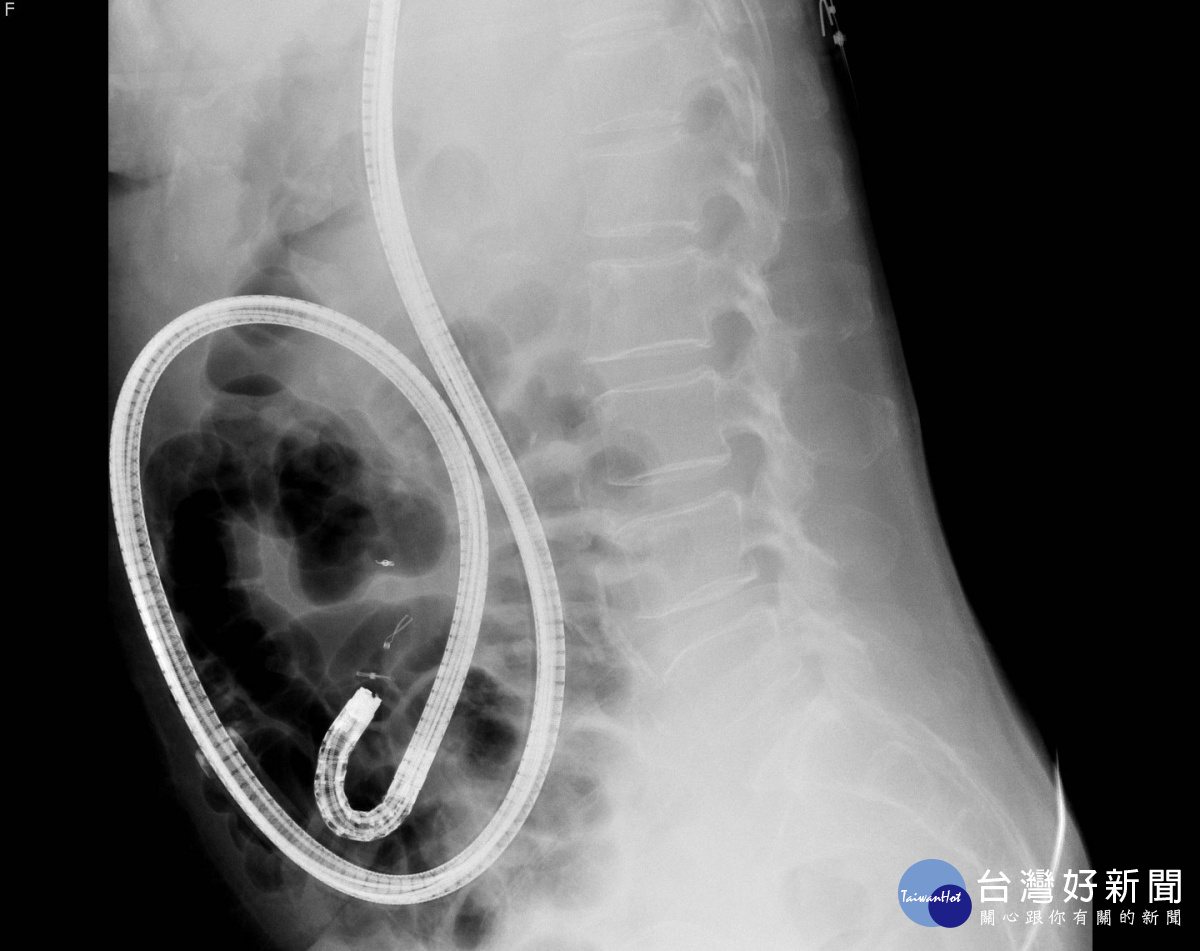

吳政輝醫師強調,「相較膠囊內視鏡只能診斷卻無法治療,氣囊輔助小腸鏡鏡檢同時,如果發現病灶可以反覆觀察、給予止血、切片取樣、或直接切除腫瘤與息肉;如需進一步手術,也可以標記病灶,方便外科開刀醫師找尋,是能對全小腸進行手術以外檢查及治療的診斷方式」。氣囊輔助小腸鏡可分為雙氣囊或單氣囊輔助,兩者原理類似,以新竹馬偕購置的單氣囊輔助小腸鏡為例,外觀與胃鏡類似,但另附一個有氣囊的外套管,隨氣囊充氣還原,固定小腸壁後往回拉,如同捲袖子一樣,藉由重覆回拉摺疊的步驟深入小腸內部檢查治療。其次,一般胃鏡、大腸鏡檢查時間約10~30分鐘,小腸鏡檢查則需耗時達3至6小時或更久,並要合併經口及經肛門兩種途徑,才可能完成全小腸檢查,但若術前已經由其他影像學檢查定位病灶位置,則可經口或經肛門擇一方式施行針對性檢查或治療。